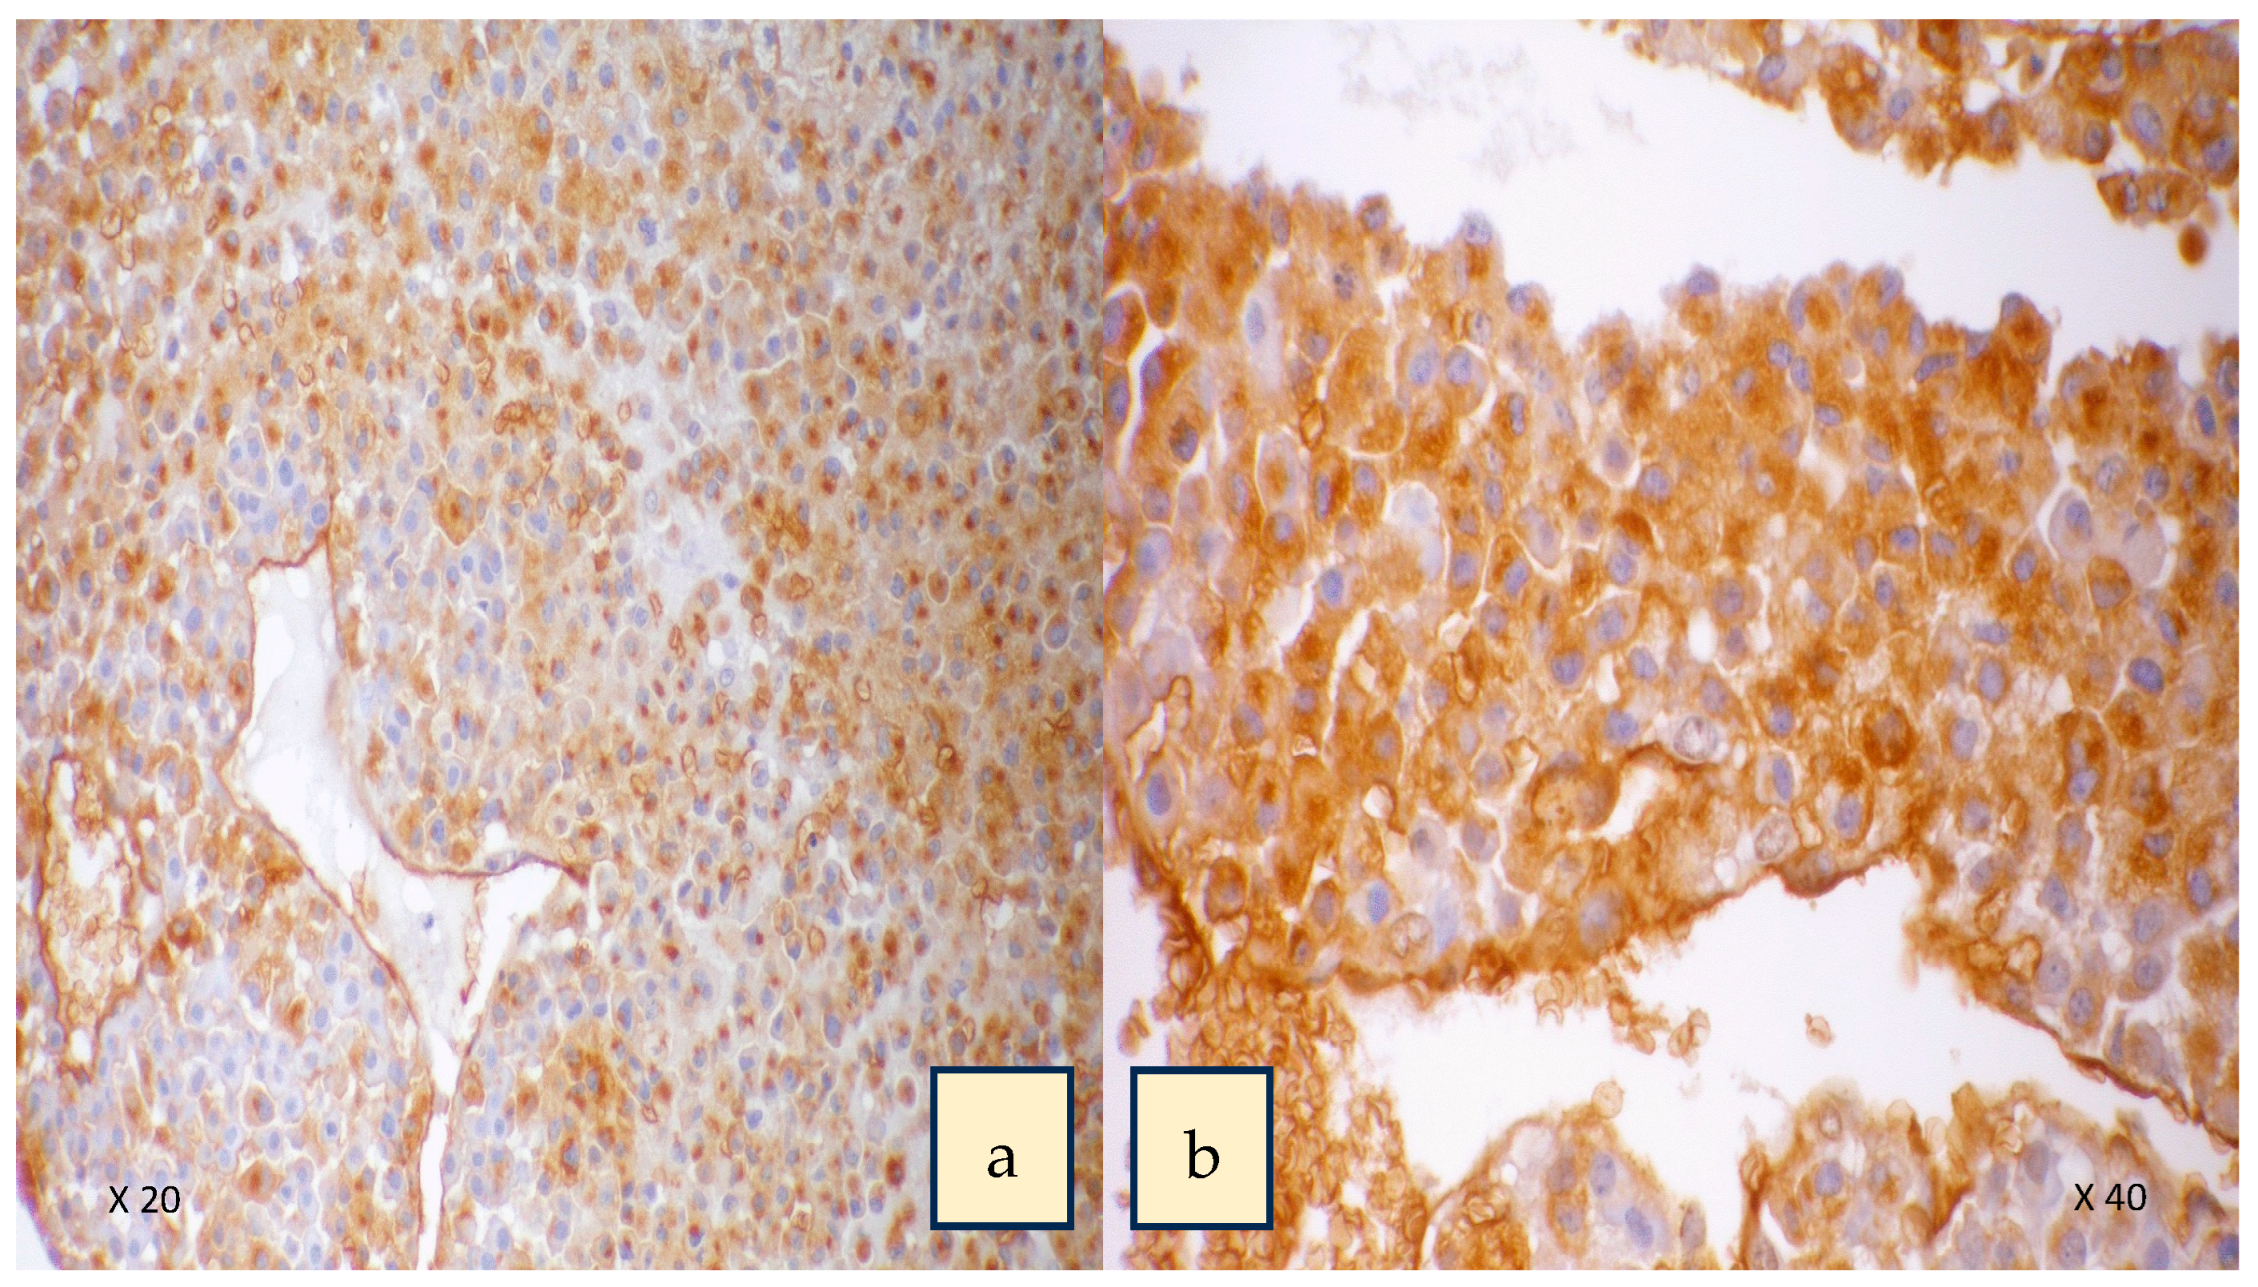

- Parameswaran, R.; Tan, W.B.; Nga, M.E.; Soon, G.S.T.; Ngiam, K.Y.; Brooks, S.A.; Sadler, G.P.; Mihai, R. Binding of aberrant glycoproteins recognizable by Helix pomatia agglutinin in adrenal cancers. BJS Open 2018, 2, 353–359. [Google Scholar] [CrossRef]

- Parameswaran, R.; Sadler, G.; Brooks, S. Helix pomatia Agglutinin Binding Glycoproteins in Thyroid Tumors. World J. Surg. 2011, 35, 2219–2227. [Google Scholar] [CrossRef]

- Lee, K.Y.; Sreenivasan, D.K.; Feng, P.; Yang, P.; Parameswaran, R. MON-LB85 Aberrant Glycan Expression Changes with the Phenotype of Follicular Thyroid Tumours. J. Endocr. Soc. 2020, 4, 2093. [Google Scholar] [CrossRef]